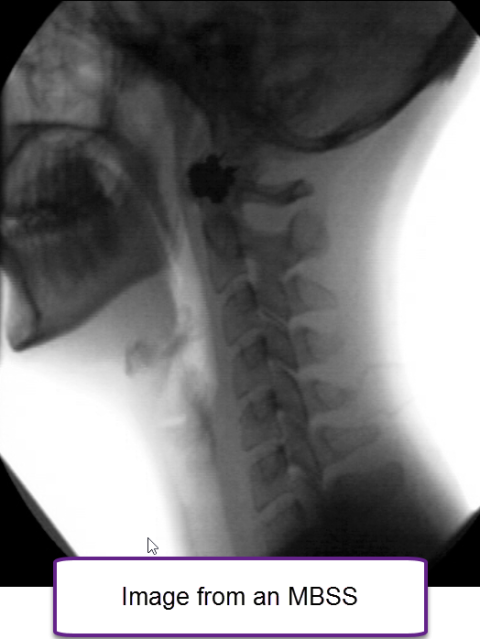

Modified barium swallow study (MBSS)

The MBSS is a fluoroscopic radiologic test performed to evaluate swallowing. It gives information on how efficiently an individual can move liquid or food from the mouth to the throat and then into the esophagus. This exam reveals if liquid or food is being aspirated (aspiration = material that goes down the wrong way, or specifically, enters the windpipe or trachea). A speech pathologist is the professional typically performing the test. The patient sits in a chair and swallows food and liquid. Everything swallowed has barium added to it. Barium material is used because it shows up on x-rays. The swallow study is recorded and the speech pathologist analyzes the study to determine if swallow structures are moving in an abnormal manner, if there is excess residue or aspiration (and why), and correlates the patient’s swallowing complaint to the observed swallowing behavior. The speech pathologist may ask the patient to perform behavioral maneuvers during the study, to try to improve swallow function. The speech pathologist may recommend swallow therapy. The speech pathologist will send a report based on study results to the referring physician.